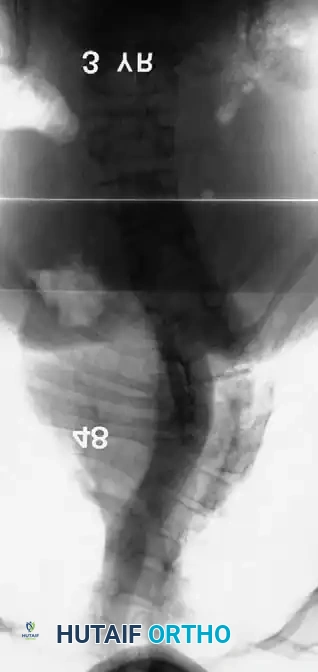

Image

Surgical planning and execution of complex congenital curve corrections.